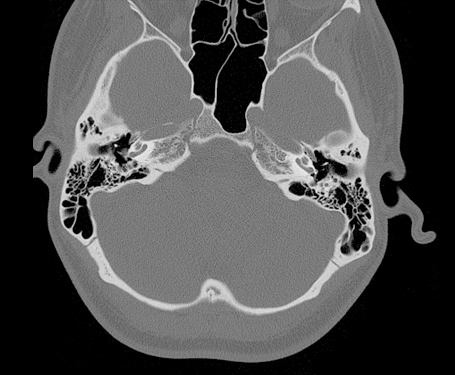

Temporal Bone